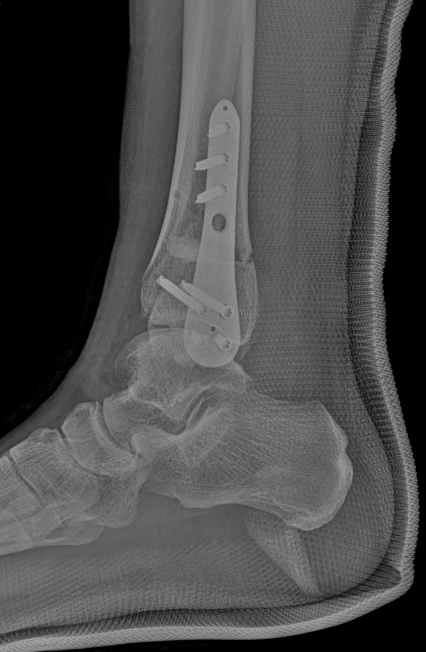

术后复查X线

术后复查侧位X线